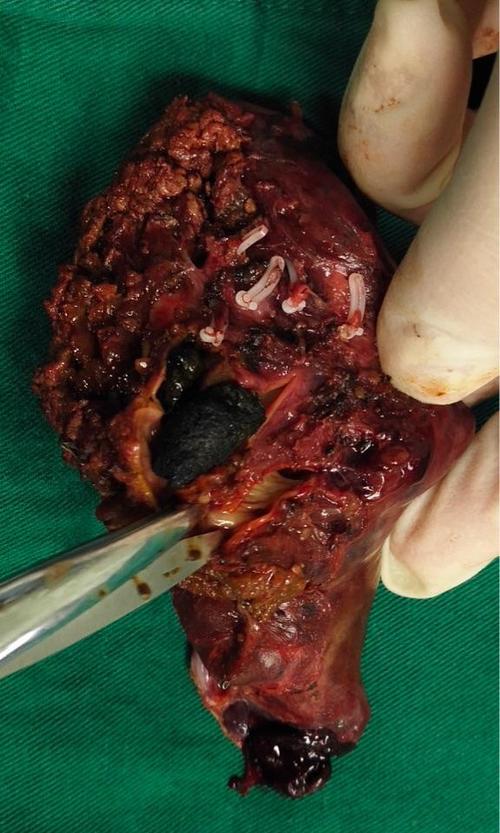

2、2. 感染症状:当肝内胆管结石引起胆道感染时,可能会刺激胆管壁,从而导致背部疼痛症状。此时,患者可能需要进一步的检查,如B超、CT等,以观察是否有肝内胆管壁的增厚、胆管内的炎症,甚至肝脓肿、肝萎缩等情况的发生。如果存在这些情况,建议及时就医,并考虑肝内胆管结石手术切除,以避免反复发作的...。

3、肝脏功能受损阶段:长期胆汁引流不畅可能导致部分肝脏萎缩或脓肿形成,此时患者可出现乏力、恶心、呕吐等症状,严重者甚至因毒素入血引发意识障碍。需注意,肝内胆管结石症状与胆总管囊肿(腹痛、腹部包块、黄疸三联征)或肝外胆管结石(腹痛、寒战高热、黄疸Charcot三联征)等疾病的典型表现不同,无统一的...。